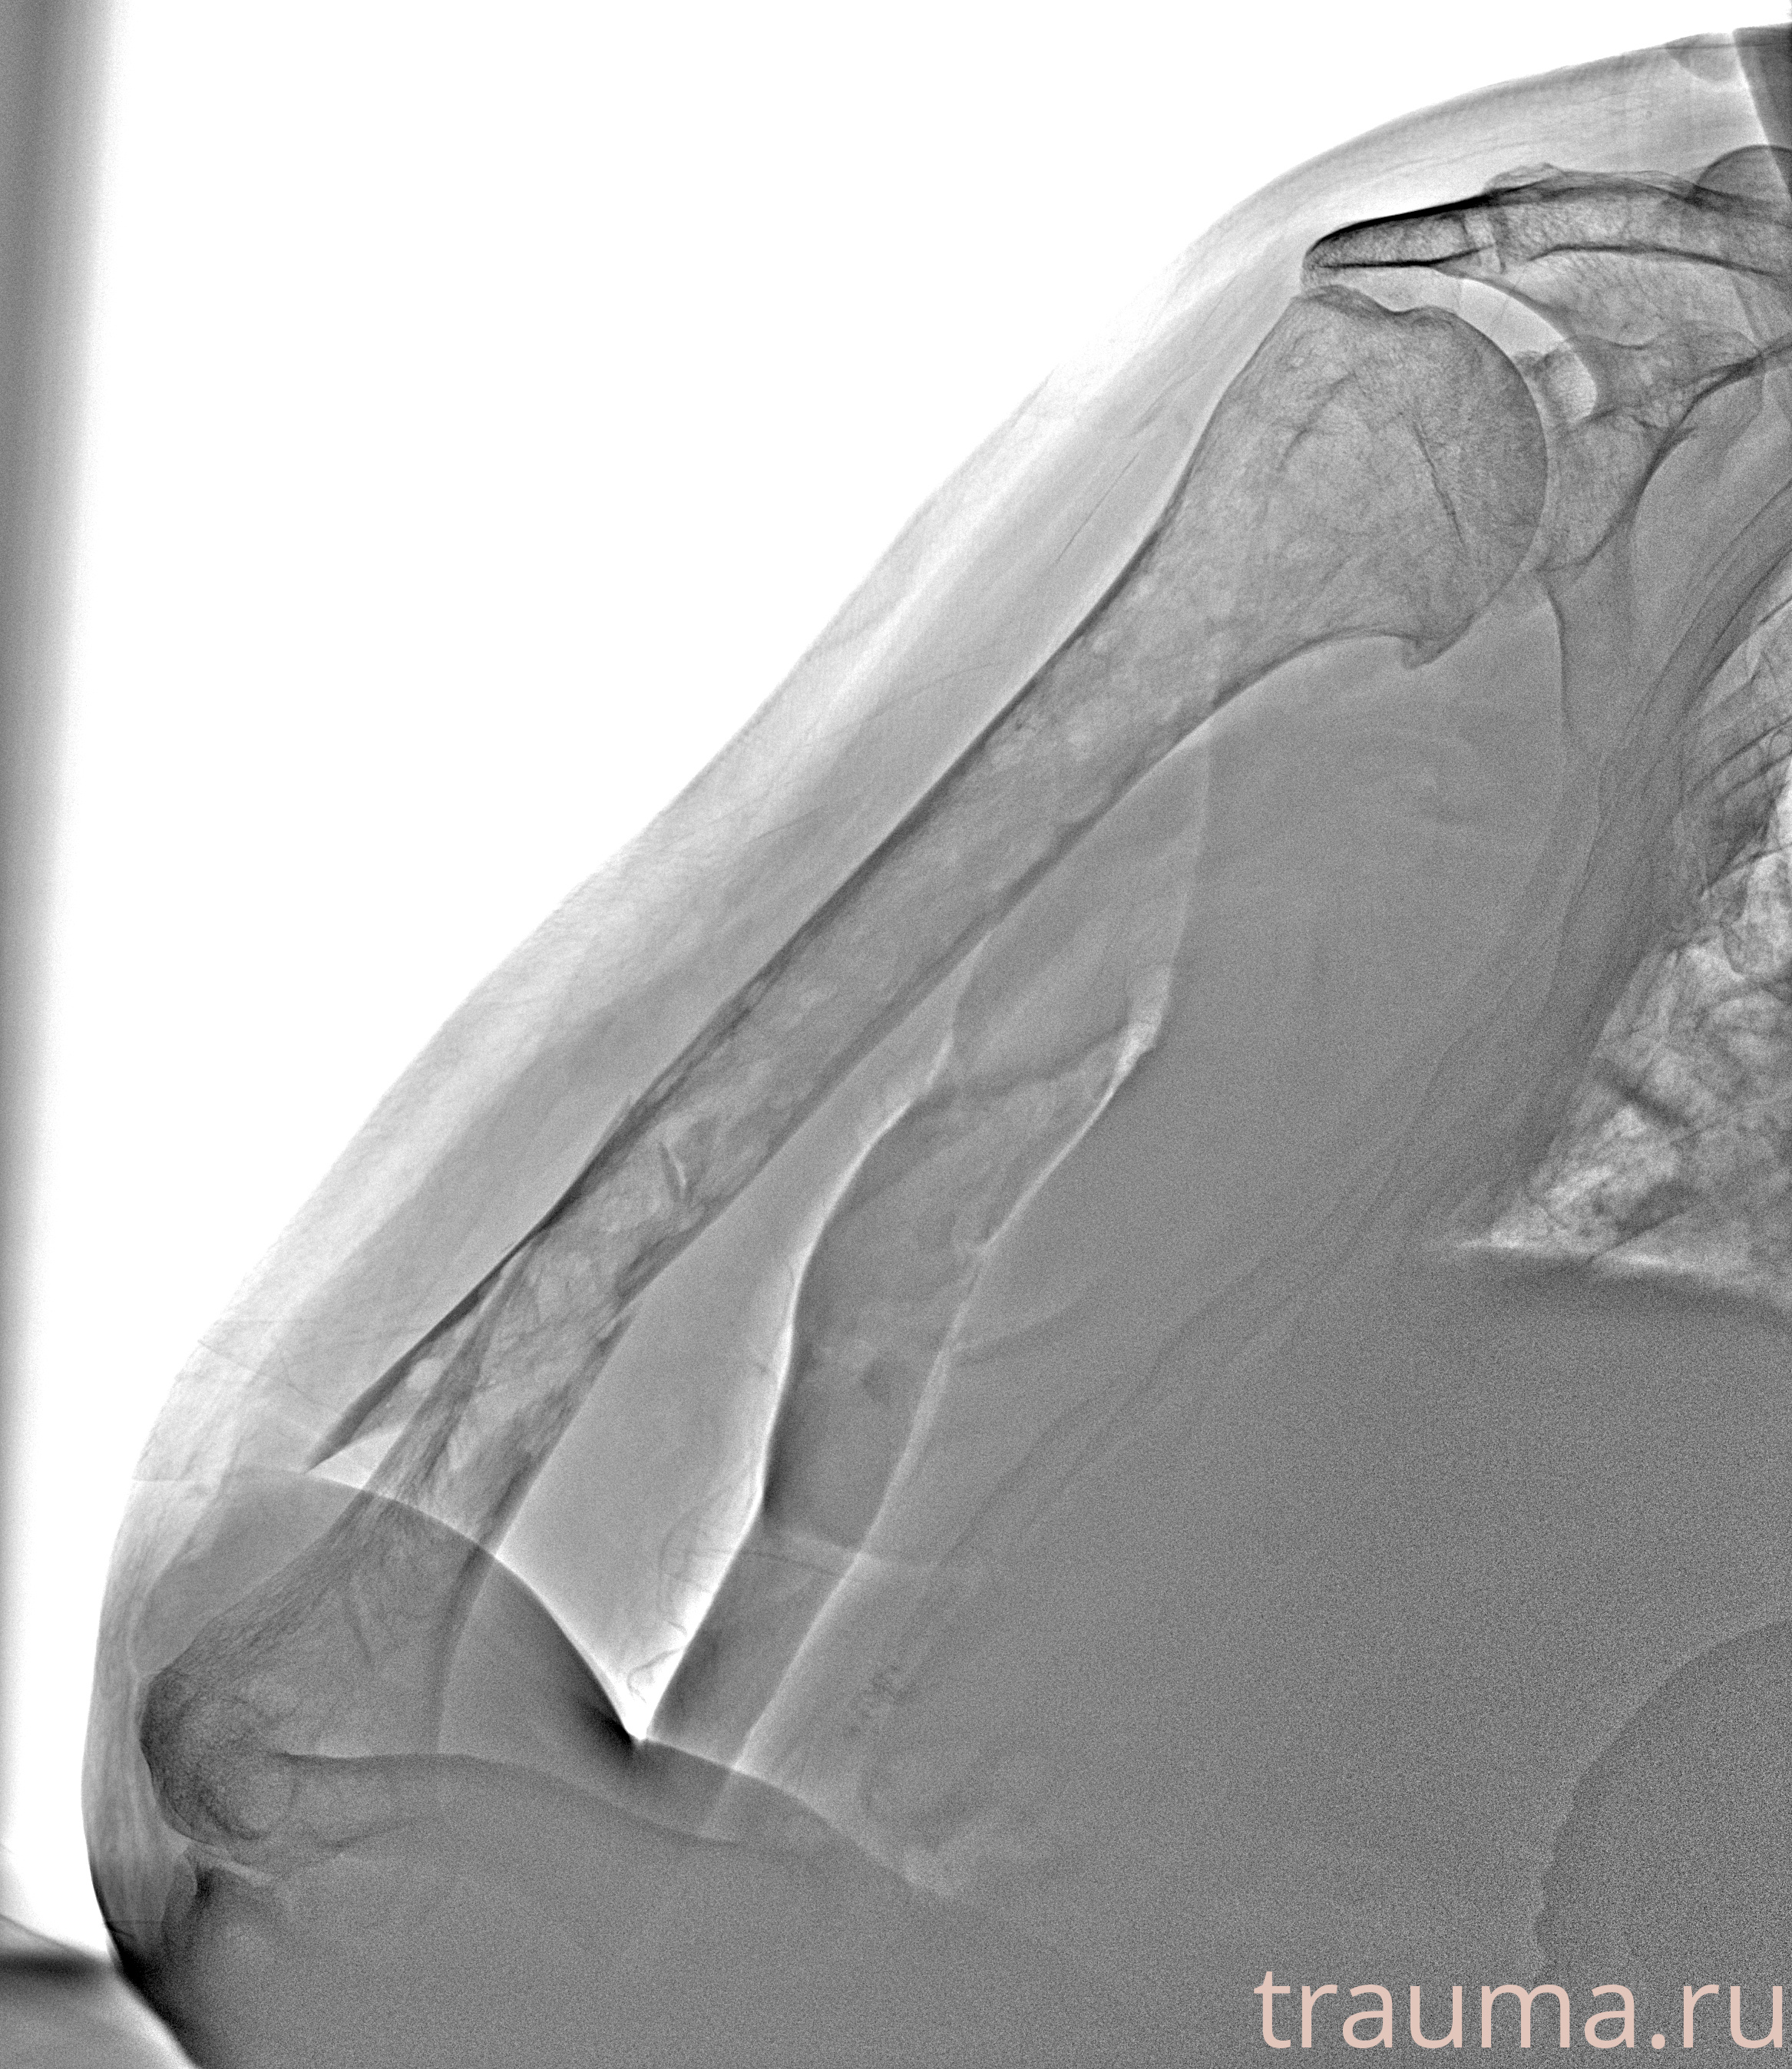

Рентген на дому: по вашему адресу приезжает врач-рентгенолог, травматолог-ортопед с мобильным рентгеновским аппаратом, проводит диагностику травмы или заболевания, делает необходимые рентгенограммы, дает рекомендации по дальнейшему лечению. Получить качественные снимки в домашних условиях возможно благодаря уникальной методике, разработанной МосРентген Центром для института  Склифосовского